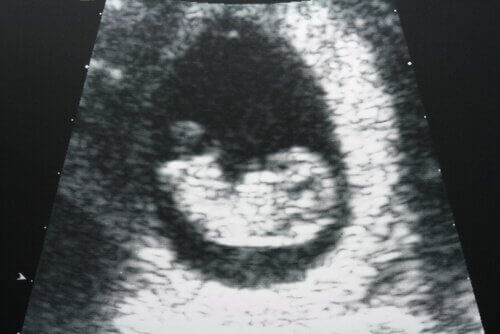

Lekarz prowadzący wykona USG transwaginalne w pierwszym trymestrze, aby upewnić się, czy kobieta wymaga przeprowadzenia późnego poronienia. Może pojawić się konieczność jego powtórzenia przed postawieniem diagnozy końcowej, jednak zależy to od wieku ciążowego.